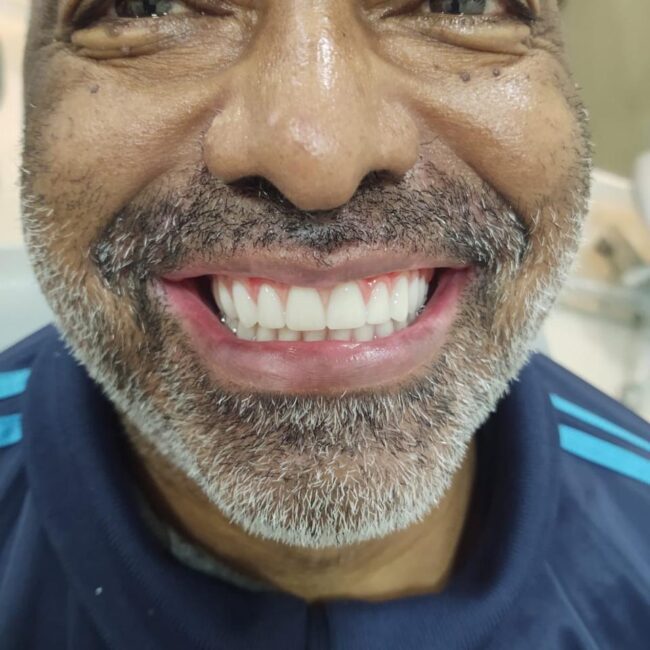

– Proporciona ao paciente a funcionalidade dental quase instantaneamente, melhorando a estética e a confiança.

– Estética Rápida: Resultados visíveis em menos tempo.

– Estética Imediata: Os pacientes podem sair da clínica com um sorriso restaurado no mesmo dia.